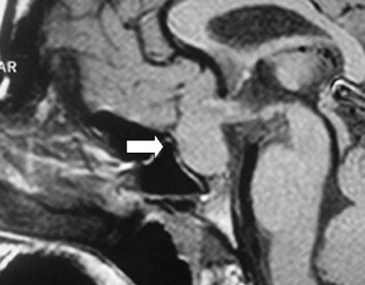

A los 17 años de edad la madre consulta por notar compromiso del estado general, decaimiento, cefalea y polidipsia importante (>4 L/d). Dentro del estudio la RNM cerebral mostró un proceso expansivo mayor a 2 cm, que comprimía el quiasma óptico, sin invasión de los senos cavernosos. Esta imagen se catalogó como macroadenoma hipofisiario intra y supraselar (Figura 1 y Figura 2). En estudio, la imagen T1 sagital sin gadolinio, mostró una silla turca de tamaño normal con un significativo aumento de volumen de la hipófisis, la cual mostró intensidad de señal normal y homogénea. El tallo hipofisiario estaba ascendido y no se reconocía claramente la señal espontánea hiperintensa de la neurohipófisis. En el corte coronal con gadolinio se evidenció claramente la glándula aumentada de tamaño, protruyendo hacia cefálico, con ocupación de la cisterna supraselar y rechazando el quiasma óptico. La impregnación del contraste es difusa y homogénea, sin defectos de captación glandulares que sugieran lesiones focales de tipo adenomatoso o de degeneración quística.